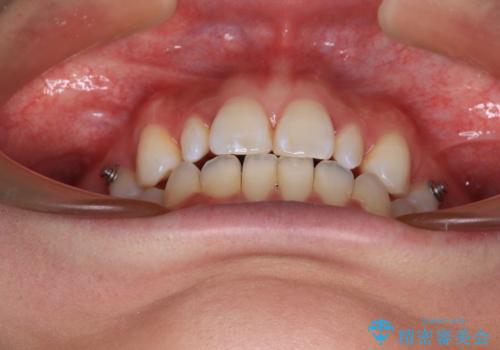

飛び出した前歯 インビザラインを用いた抜歯矯正治療

- 前方に飛び出した前歯を気にして来院された患者様です。

遠方の地元へ転居する予定があるとのことで、インビザラインによる治療を希望されていらっしゃいました。

上下前歯同士の距離が離れているため、上顎左右第一小臼歯2本を抜歯することで前突を改善することとしました。

しかしながら、左右ともに側切歯が矮小歯であるため、矯正治療で矮小歯前後にスペースを作り、矯正治療後にオールセラミッククラウンにて補綴治療を行うこととしました。